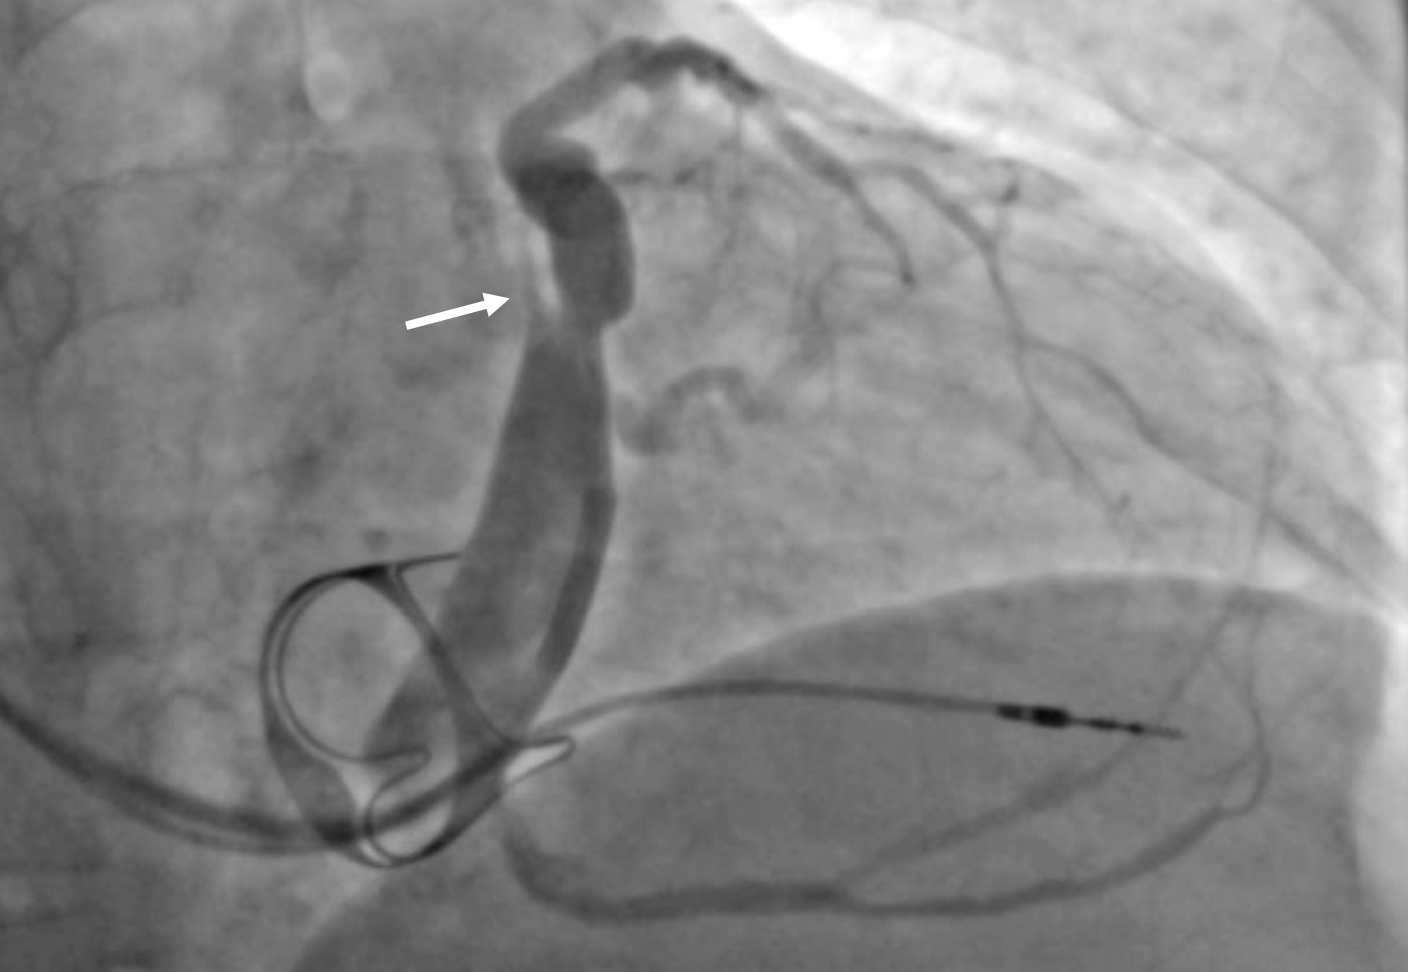

Elimination of a perimitral atrial flutter circuit can be particularly challenging and incomplete linear ablation may perpetuate flutter; therefore, we do not recommend routine mitral isthmus ablation except when inducible or in the presence of advanced atrial fibrosis. All available approaches present challenges, again due to difficulty achieving lesion transmurality. The 2 main strategies for achieving mitral block are an anterior line connecting either the right or left superior PV antrum to the anterior mitral annulus superior to the left atrial appendage (LAA), or a lateral line connecting the left PV antra to the lateral mitral annulus inferior to the LAA. The anterior path is hindered by Bachmann’s bundle, the thickest portion of the human atrium. If endocardial block is achieved without block across Bachmann’s bundle, a biatrial reentry circuit can be observed. This has been verified in epicardial mapping studies.29,30 When endocardial ablation of Bachmann’s bundle cannot be achieved and flutter persists, options are creation of an alternate mitral line or epicardial ablation. A portion of the anterior left atrium can be reached from the pericardial space, though the aortic root limits accessibility to the region near the right PVs. For this reason, our usual approach is a lateral line. The 2 challenges in the lateral approach are the coronary sinus (CS) and VOM. When ablating along the lateral mitral annulus, blood flow through the CS reduces epicardial tissue heating via convective loss of energy.31 Because of this, epicardial ablation within the CS itself is nearly always required to achieve lateral mitral block. In some instances, the CS musculature itself may serve as a bridge over a lateral mitral line (Figure 1). This problem can be easily addressed by ablation within the CS, and at times, circumferential ablation is needed. A more challenging problem is epicardial bridging utilizing the VOM (Figure 2)32, which can actually cause the lateral mitral annulus adjacent to the line of block to become a passive part of the flutter circuit (Figure 3, Video 1). Our strategy to address this is to ablate both the anterior and posterior aspects of the left lateral ridge from the level of the superior to inferior PVs (Figure 4). If this does not abolish VOM conduction, then targeting the touch down area of the VOM may be effective (Figure 5). If endocardial approaches are not effective, VOM ethanol infusion is very likely to be successful but has some risk of perforation and pericardial bleeding. Finally, ablation from the pericardial space along the sulcus between the left PVs and LAA can be performed. Systematic ablation of the VOM by ethanol infusion has shown promising results.33-35

Correction: This article was corrected on May 23, 2022, to fix incorrect placement of an arrow in Figure 2. Figure 2 has been replaced.